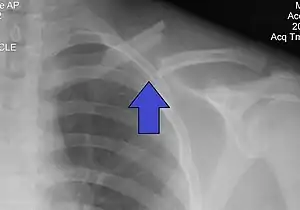

The basic method to check for a clavicle fracture is by an X-ray of the clavicle to determine the fracture type and extent of injury. In former times, X-rays were taken of both clavicle bones for comparison purposes. Due to the curved shape in a tilted plane X-rays are typically oriented with ~15° upwards facing tilt from the front. In more severe cases, a computerized tomography (CT) or magnetic resonance imaging (MRI) scan is taken. However, the standard method of diagnosis through ultrasound imaging performed in the emergency room may be equally accurate in children.[6]

It is often caused by a fall onto a shoulder, outstretched arm, or direct trauma.[1][3] The fracture can also occur in a baby during childbirth.[1] The middle section of the clavicle is most often involved.[3] Diagnosis is typically based on symptoms and confirmed with X-rays.[2]